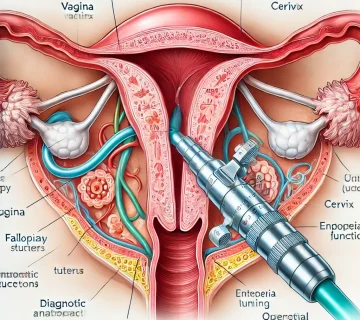

۱. درمان آتروفی واژن (خشکی واژن و عوارض یائسگی)

آتروفی واژن که اغلب ناشی از کاهش سطح استروژن (بهویژه در دوران یائسگی) است، میتواند باعث خشکی، خارش، سوزش و درد در هنگام مقاربت شود. پلاسماتراپی با تحریک تولید کلاژن و افزایش خونرسانی به دیوارههای مخاطی واژن، به بازسازی بافتهای نازک شده کمک کرده و با بازگرداندن رطوبت و انعطافپذیری طبیعی به بافت، علائم آزاردهنده این دوران را بهطور چشمگیری کاهش میدهد.

۲. کمک به درمان بیاختیاری ادرار استرسی (SUI)

بیاختیاری ادرار استرسی (نشت ادرار هنگام سرفه، عطسه یا فعالیت بدنی) به دلیل ضعف بافتهای حمایتکننده مجرای ادرار و عضلات کف لگن ایجاد میشود. پلاسماتراپی از طریق تقویت و بازسازی بافتهای پیوندی اطراف مجرای ادرار و گردن مثانه، به بهبود حمایت ساختاری از مثانه کمک کرده و در بسیاری از موارد، باعث کاهش یا رفع نشت ادرار بدون نیاز به مداخلات جراحی پیچیده میشود.

۳. بهبود سریعتر برشهای اپیزیوتومی و زخمهای پس از زایمان

دوران نقاهت پس از زایمان میتواند برای بسیاری از مادران چالشبرانگیز باشد. پلاسماتراپی با بهرهگیری از فاکتورهای رشد طبیعی، روند تکثیر سلولی و ترمیم زخمهای ناشی از اپیزیوتومی (برش زایمان) یا پارگیهای حین زایمان را تسریع میکند. این فرآیند باعث میشود بافت آسیبدیده با کیفیت بهتری ترمیم شده و درد و ناراحتی پس از زایمان کاهش یابد.

۴. کنترل و درمان عفونتهای مزمن واژینال

یکی از ویژگیهای کمتر شناختهشده اما بسیار ارزشمند پلاسما، خاصیت ضدعفونیکنندگی و آنتیباکتریال طبیعی آن است. در مواردی که بیمار با عفونتهای مکرر و مقاوم به درمانهای دارویی (مانند آنتیبیوتیکها) مواجه است، پلاسماتراپی میتواند با تقویت سیستم دفاعی مخاط واژن و ایجاد محیطی که برای رشد باکتریهای مضر نامناسب است، به کنترل عفونتهای مزمن و بازگرداندن تعادل فلور طبیعی واژن کمک کند.